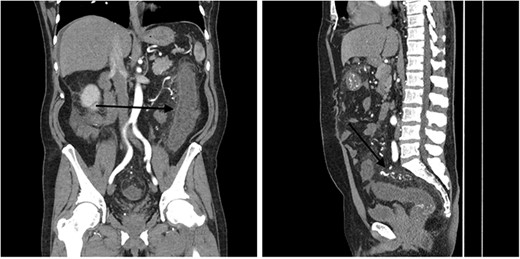

A 51-year-old male patient presented to the emergency department with 24 hours of severe abdominal pain and rectal bleeding, as well as 4 months history of non-mucous diarrhoea with stool frequency of up to 12 episodes per day. He had a background of poorly differentiated adenocarcinoma of the ascending colon (T3N0M0), which was treated with laparoscopic right hemicolectomy 1 year prior to this presentation. His follow-up colonoscopy 6 months prior to admission demonstrated evidence of diverticular disease and colitis although biopsies were normal. On admission, the patient was haemodynamically stable and physical examination did not reveal signs of peritonism. Laboratory studies demonstrated a haemoglobin drop of 4 g/dl (15.9–10.8 g/dl) but no evidence of abnormal coagulation. Stool samples were negative for infectious causes. The diagnosis of ischaemic colitis was made by contrast-enhanced computed tomography (CT) scan with CT angiography, which revealed AVMs in the territory of SMA and IMA and acute massive congestive ischaemic colitis affecting remaining colon and rectum (Figs 1 and 2).

Contrast-enhanced abdominal CT images of superior mesenteric AVM causing acute congestive ischaemic colitis affecting transverse colon.